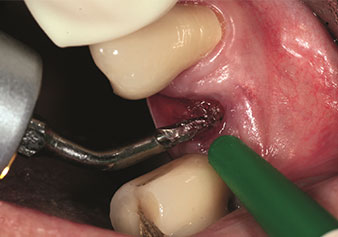

Après la préparation des sinus maxillaires à l'aide du jeu d'inserts correspondant (Fig. 3), le nouvel insert Z35P (Fig. 4) est utilisé pour l’élévation de la membrane par technique hydrodynamique. Le même jeu d'inserts peut aussi être utilisé pour la préparation piézochirurgicale du lit implantaire en augmentant les diamètres (Figures 3 et 4 fournies avec l'autorisation du Dr Mario Kirste, Francfort-sur-l’Oder).

Préparation du lit implantaire à l'aide de l'insert I4P

Fig. 3 : Préparation du lit implantaire à l'aide de l'insert I4P.

Préparation du plancher du sinus maxillaire et élévation de la membrane de Schneider (Insert Z35P)

Fig. 4 : Préparation du plancher du sinus maxillaire et élévation de la membrane de Schneider (Insert Z35P).